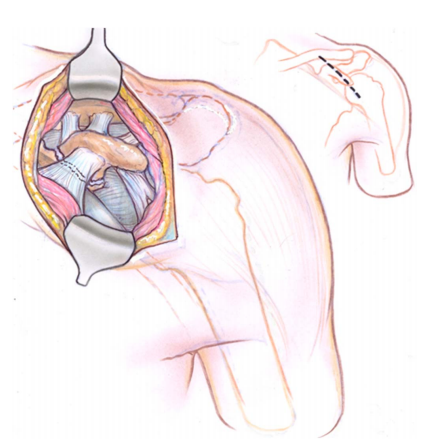

初始切口以 Langer 线的方向直接对准喙突上方的三角肌胸大肌沟(图 1)。

图 1. 尸体解剖显示前入路至喙突时 Langer 线的切口 (A) 和分离 (B) 标志。

这种策略具有美观性,并且可以延伸至正式的三角肌胸大肌入路,以处理前侧肩盂的相关病变。切口向下延伸穿过皮下组织至锁胸筋膜。触诊喙突,在其正上方切开筋膜(图 2)。

图 2. 采用前入路至喙突的尸体标本。标记有喙锁韧带 (CCL)、喙肩韧带 (CA) 和联合腱 (CT)。

在喙突远端,于胸大肌和三角肌之间分离间隙,同时切口从喙突向头侧延伸至锁骨,穿过胸小肌。然后使用剥离器从喙突尖沿其头侧斜面进行钝性分离。

根据骨折类型和受损结构,这种分离可以直接到达骨折部位,或者到达从喙突基底延伸到锁骨下表面的坚固韧带,即由锥状韧带(内侧)和斜方韧带(外侧)组成的 CCL 复合体。此时,外科医生可以识别附着在喙突上的软组织结构(喙肩韧带、联合腱和 CCL)(图 3)。

图 3. 通过前入路,可以清晰地看到骨折线和韧带附着点。当韧带完整时,外科医生应围绕这些韧带进行分离,直到看清骨折并能够进行解剖复位。